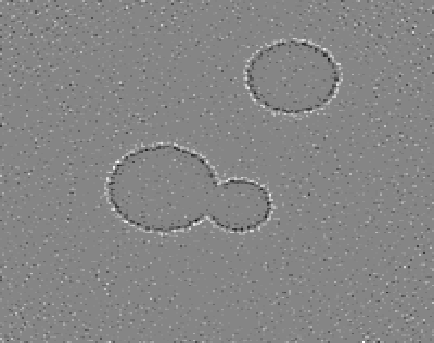

4.1 Reconstruction of the Laplacian feature map

We first investigate the feasibility of the proposed approach for recovering the Laplacian of the initial image. For our first experiment, we use a phantom image, which is defined as a characteristic function of the union of three discs and has the size N×N𝑁𝑁N\times N with N=200𝑁200N=200, cf. Figure 1(a). Since, according to the sampling condition (2.5), full aliasing free angular sampling requires πNs=472𝜋subscript𝑁𝑠472\lceil\pi N_{s}\rceil=472 samples in the s𝑠s-variable, we computed tomographic data at 2Ns+1=3012subscript𝑁𝑠13012N_{s}+1=301 equally spaced signed distances s[1.5,1.5]subscript𝑠1.51.5s_{\ell}\in[-1.5,1.5] and at Nφ=40subscript𝑁𝜑40N_{\varphi}=40 equally spaced directions in [0,π)0𝜋[0,\pi). This data is properly sampled in the s𝑠s-variable, but undersampled in the angular variable φ𝜑\varphi, cf. Figure 1(b).

From this data, we computed the approximate Laplacian reconstruction, shown in Figure 1(c), using the standard FBP algorithm in combination with the LoG-filtered data uLoGsyΘsubscript𝑠subscript𝑢LoGsubscript𝑦Θu_{\rm LoG}\circledast_{s}y_{\Theta} that we computed in a preprocessing step using the LoG data filter from Proposition 3.4. It can be clearly observed that FBP introduces prominent undersampling artefacts (streaks), so that many edges in the calculated feature map are not related to the actual image features. This shows, that the edge maps computed by FBP (from undersampled data) can include unreliable information and even falsify the true edge information (since artefacts and actual edges superimpose). In a more realistic setup, this could be even worse, since artefacts may not be that clearly distinguishable from actual edges.

Refer to caption

(a) Phantom

(b) CT data

(c) FBP-LoG reconstruction

Figure 4.1: Reconstruction of the Laplacian feature map using FBP. The phantom image of size 200×200200200200\times 200 consisting of a union of three discs (1(a)) and the corresponding angularly undersampled CT data, measured at 40 equispaced angles in [0,π)0𝜋[0,\pi) and properly sampled in the s𝑠s-variable with 301301301 equispaced samples s[1.5,1.5]subscript𝑠1.51.5s_{\ell}\in[-1.5,1.5] (1(b)). Subfigure (1(c)) shows the Laplacian of Gaussian (LoG) reconstruction using the standard FBP algorithm. It can be clearly observed that FBP introduces prominent streaking artefacts that are due to the angular undersampling.